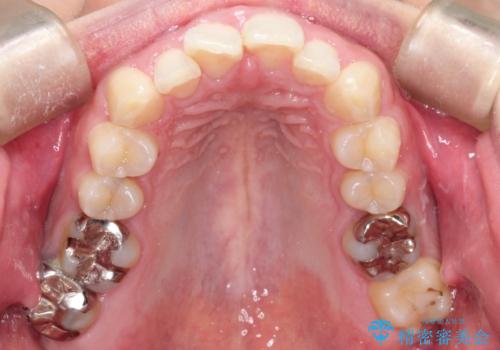

前歯が前後反対にかんでいる インビザラインによる矯正

- 前歯のがたつきを気にされて来院されました。

上顎の前から二番目の歯が内側に入り込んでおり、前後反対にかんでいる状態でした。

歯と歯の間にわずかに隙間を作り並べる計画としました。